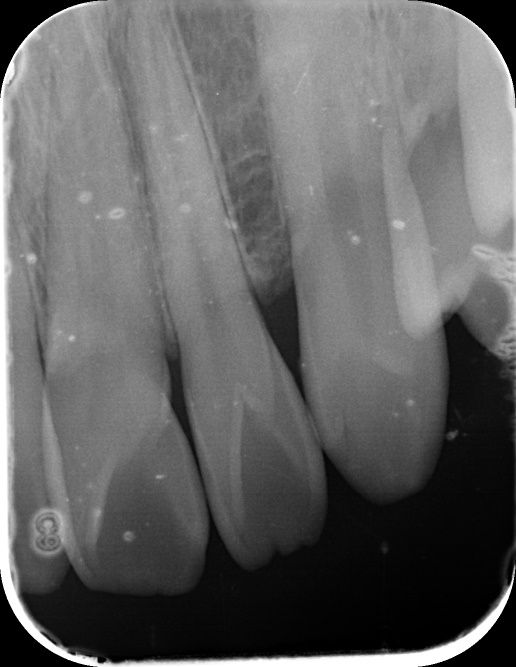

앞니 사이 인접면 충치가 있나요?(사진 첨부)

12, 11, 21, 22 번 4개 앞니 치아들에 대해서

• 4번 째 사진

엑스레이 상으로는 11과 12번의 사이, 21과 22의 사이에 충치가 있는 것으로 보이는데 맞나요?

실제로 바람불어서 긁어봐야 판단이 설 것 같긴한데 일단 엑스레이만 봐서는 관리를 잘한다고 해서 진행을 멈출 사이즈의 충치는 아닌 것 같은데, 지금처럼 인접면 충치의 경우에는 충치부위에 기구접근이 안되기 때문에 딱 충치부분만 제거를 할 수가 없어요. 그래서 좀 더 커질때까지 두고 보자vs지금 치료를 하자 이렇게 나뉜 것 같은데 원래 정석적으로는 바로 치료를 하는게 맞긴 합니다만, 치료를 해서 얻는 것보다 정상치질을 더 제거해야해서 잃는 실이 더 많다고 판단이 되면 좀 더 있다가 하기도 합니다. 이런 애매한 경우는 환자분께서 결정을 하시면 될 것 같습니다.

1. 법랑질 수준에 국한된 충치입니다.

2. 심미적으로 해당 부위가 검게 보이지 않는다면 관리를 하면서 지켜볼 수도 있습니다. 다만 겉으로 보기에는 검게 보인다면 치료를 하는 것이 맞으며 이는 심미적인 이유 때문입니다.

3. 11, 21 모두 치아에 일부 충치가 보입니다. 따라서 2곳 모두 치료해야할 것으로 보입니다.

엑스레이 상으로는 충치가 크게 보이진 않습니다. 저정도라면 저도 일단은 관리를 잘하시면서 지켜보라고 할것같습니다.

사진으로 보기에는 초기 우식이 보이기는 합니다. 하지만 ㅣㅊ료여부는 육안으로 확인을 해야알수가 있어요.

사진응 앞뒤가 겹쳐진 2차원 모잉야지만 충치는 3차원 공간으로 분석을 해야 하기 때문이에요.